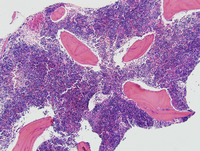

Bone Marrow Core Biopsy

Bone marrow core biopsy showing hypercellular marrow with erythroid hyperplasia